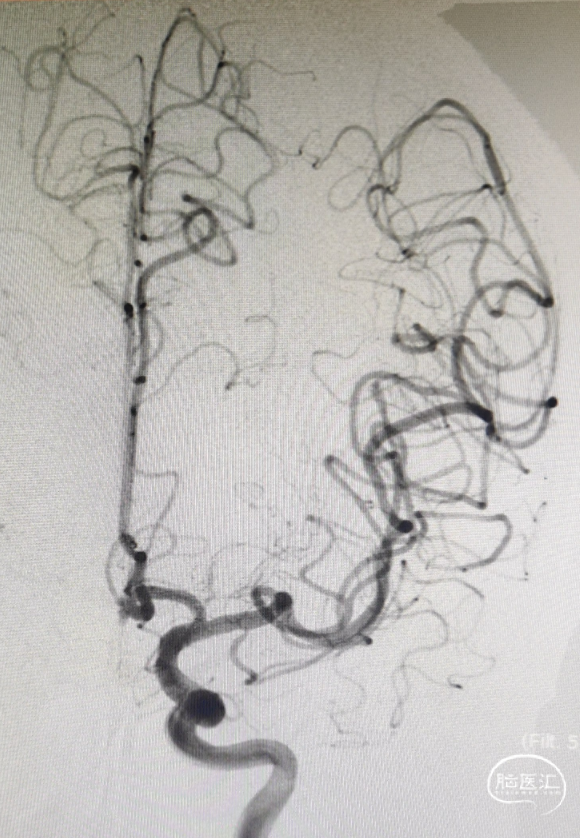

影像信息

前交通微小动脉瘤,伴多个子囊

尺寸:1.6*2.1mm

患者右侧大脑前动脉发育纤细

术后影像

动脉瘤致密栓塞,瘤腔内血栓形成;各分支血管显影正常。